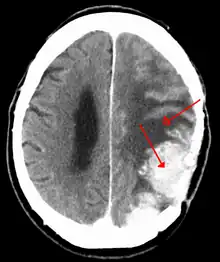

| A contrast-enhanced CT scan of the brain, demonstrating the appearance of a meningioma | |

Meningiomas are visualized readily with contrast CT, MRI with gadolinium,[22] and arteriography, all attributed to the fact that meningiomas are extra-axial and vascularized. CSF protein levels are usually found to be elevated when lumbar puncture is used to obtain spinal fluid. On T1-weighted contrast-enhanced MRI, they may show a typical dural tail sign absent in some rare forms of meningiomas.[17]